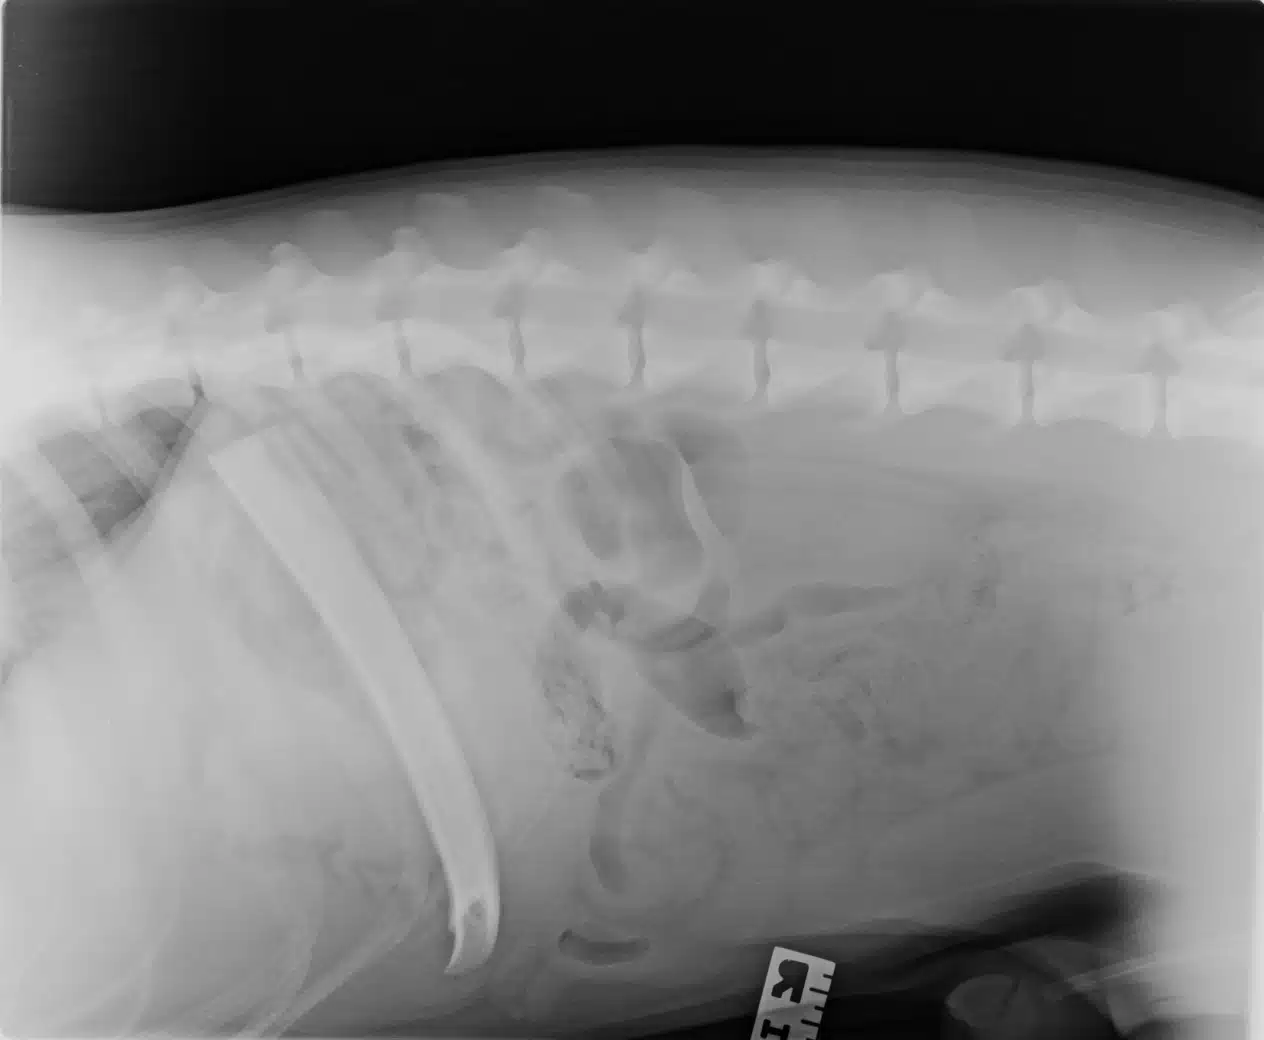

Una radiografía o ecografía para localizar el hueso.